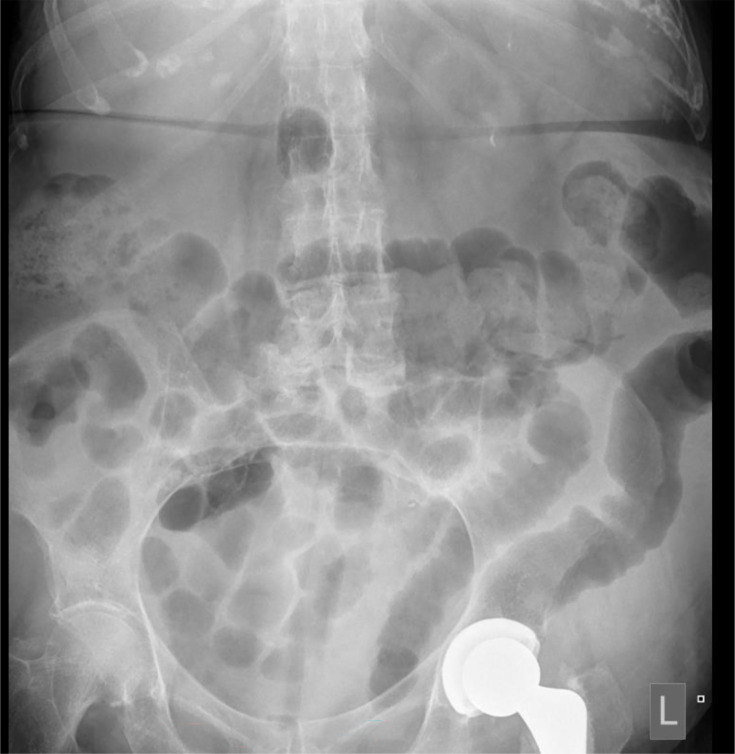

艰难梭菌(以前称为艰难梭菌)是卫生保健相关感染的一个重要原因,其症状从腹泻和腹痛到假膜性结肠炎和中毒性巨结肠。严重疾病可造成严重的发病率和死亡率风险,应被视为医疗紧急情况。一种新的艰难梭菌核型(995核型)的出现,估计死亡率为20%,促使人们重新审查有关处理严重艰难梭菌感染(CDI)的证据和指南。关于CDI管理的国际指南在一线抗生素选择方面各不相同。由于对耐药性的担忧,甲硝唑不再被推荐作为一线药物,万古霉素和非达霉素现在被推荐作为一线药物。抗生素治疗应结合良好的支持措施和早期考虑手术治疗。粪便微生物群移植可用于复发性CDI,并可用于严重疾病。严重的CDI是对公共卫生的重大持续威胁,进一步研究有效的管理对于确保患者获得最佳可能结果至关重要。

Clostridioides difficile (formerly known as Clostridium difficile) is a significant cause of healthcare-associated infection with symptoms ranging from diarrhoea and abdominal pain to pseudomembranous colitis and toxic megacolon. Severe disease can pose a significant morbidity and mortality risk and is to be considered a medical emergency. The emergence of a new C. difficile ribotype with an estimated mortality rate of 20% (ribotype 995) has prompted a re-review of the evidence and guidelines around managing severe C. difficile infections (CDI). International guidance on the management of CDI varies regarding first-line antibiotic choice. Metronidazole is no longer favoured as first line due to concerns around resistance, and vancomycin and fidaxomicin are now recommended as first line options. Antibiotic therapy should be used in conjunction with good supportive measures and early consideration of surgical management. Faecal microbiota transplant can be utilized in recurrent CDI and may be useful in severe disease. Severe CDI is a significant ongoing threat to public health, and further research into effective management is essential to ensure the best possible outcomes for patients.